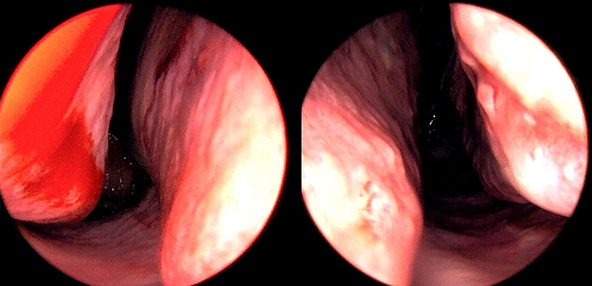

본 사진은 의료기관에서 진료를 본 환자이고, 전후 사진 인물이 동일인이며,동일조건에서 촬영이 되었습니다.